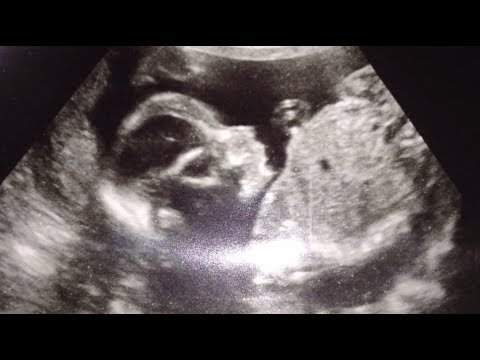

How Is Your Baby's Due Date Determined? - Pregnancy Due Date Calculator Ovulation - In this week's 'Did You Know' we're learning 'when' to expect when you're expecting - as in how a baby's due date is determined.

Pregnancy Tips : How to Calculate the Due Date From the Date of Conception - Pregnancy Due Date Calculator Ovulation - Calculating the due date from the date of conception can actually be put into a formula based on the last menstrual period before you became pregnant.

Pregnancy Due Date Calculator Wheel Chart and Ovulation Calendar - Pregnancy Due Date Calculator Ovulation - This innovative design of Pregnancy Due Date Calculator Wheel Chart provides very useful information such as Mean Fetal length, weight, Due Date etc.

Baby Health : How to Calculate When a Baby Is Due - Pregnancy Due Date Calculator Ovulation - Calculating a baby's due date can be tricky, but the last day of the last menstrual period is often considered day one of a child's gestational age. Determine the ...